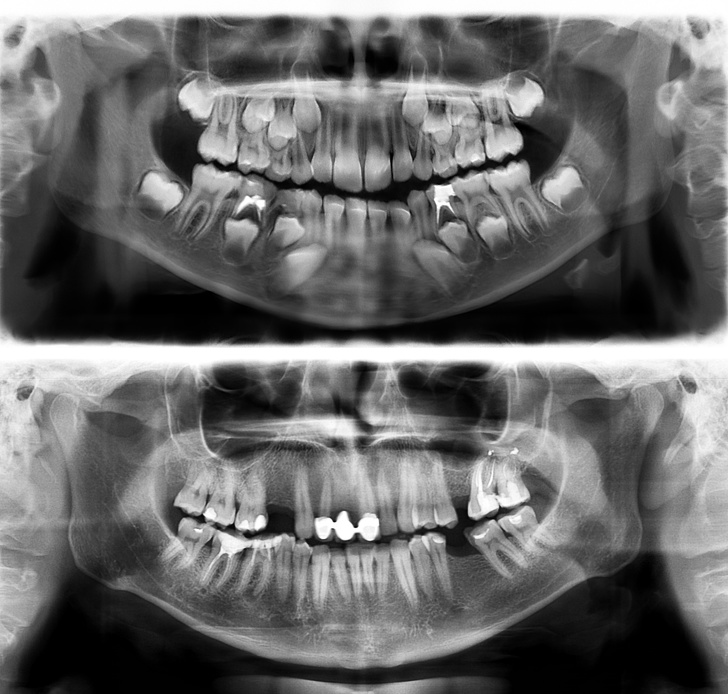

#1. The teeth of a person who is 7 (the photo on top) and a person who is 30 (the photo on the bottom)